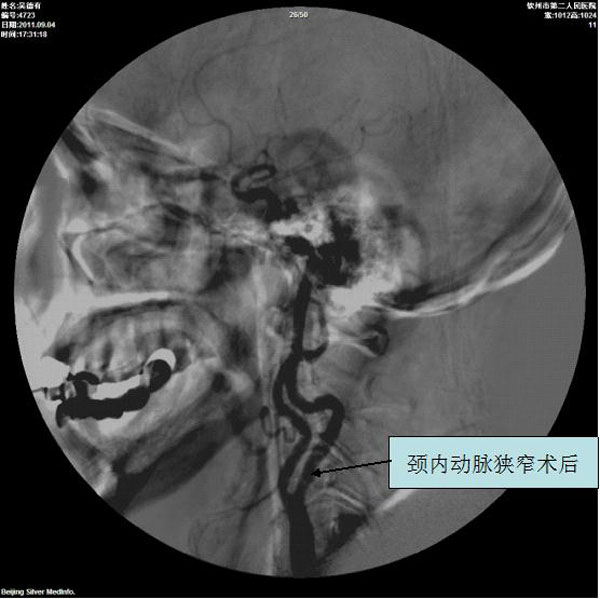

颈内动脉狭窄术后

颈动脉、椎动脉支架植入术

1.无症状动脉管径狭窄程度>70%。

2.有一过性缺血发作(TIA)或脑卒中发作症状,血管管径狭窄程度>50%。